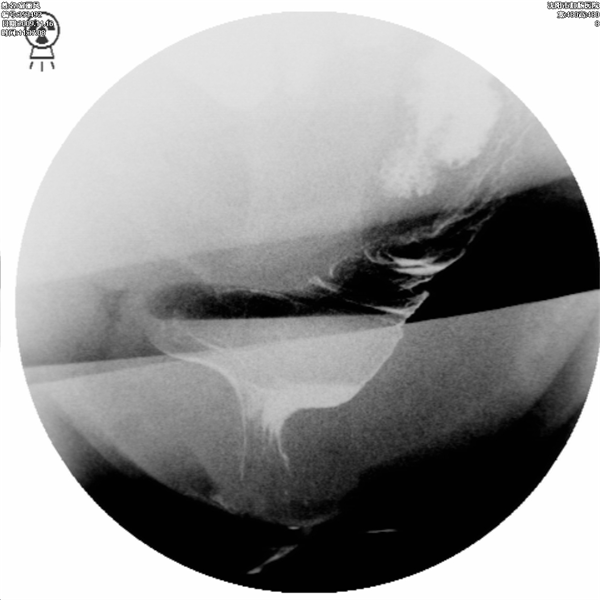

排便造影就是将钡剂模拟粪便灌入直肠内,患者坐在易透X光的排便器上,在患者排便的过程中,多次摄片或录像,以观察肛管、直肠的影像学改变,动态观察钡剂排出(模拟排便)过程中肛门和直肠的功能变化。排便造影能为会阴下降、直肠前突、直肠前壁粘膜脱垂、内套叠、盆底疝、内脏下垂、耻骨直肠肌肥厚等疾病的诊断及鉴别诊断提供可靠的依据.

直肠前突合并会阴下降

直肠前突合并直肠前壁粘膜脱垂